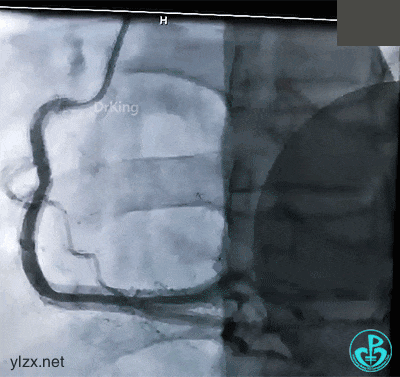

治疗过程

抽吸导管反复抽吸无效,前降支近端血栓无明显改变。送入Guidezilla,进入血栓部位,10ml注射器反复抽吸,抽出了类似脂肪组织样的物质。